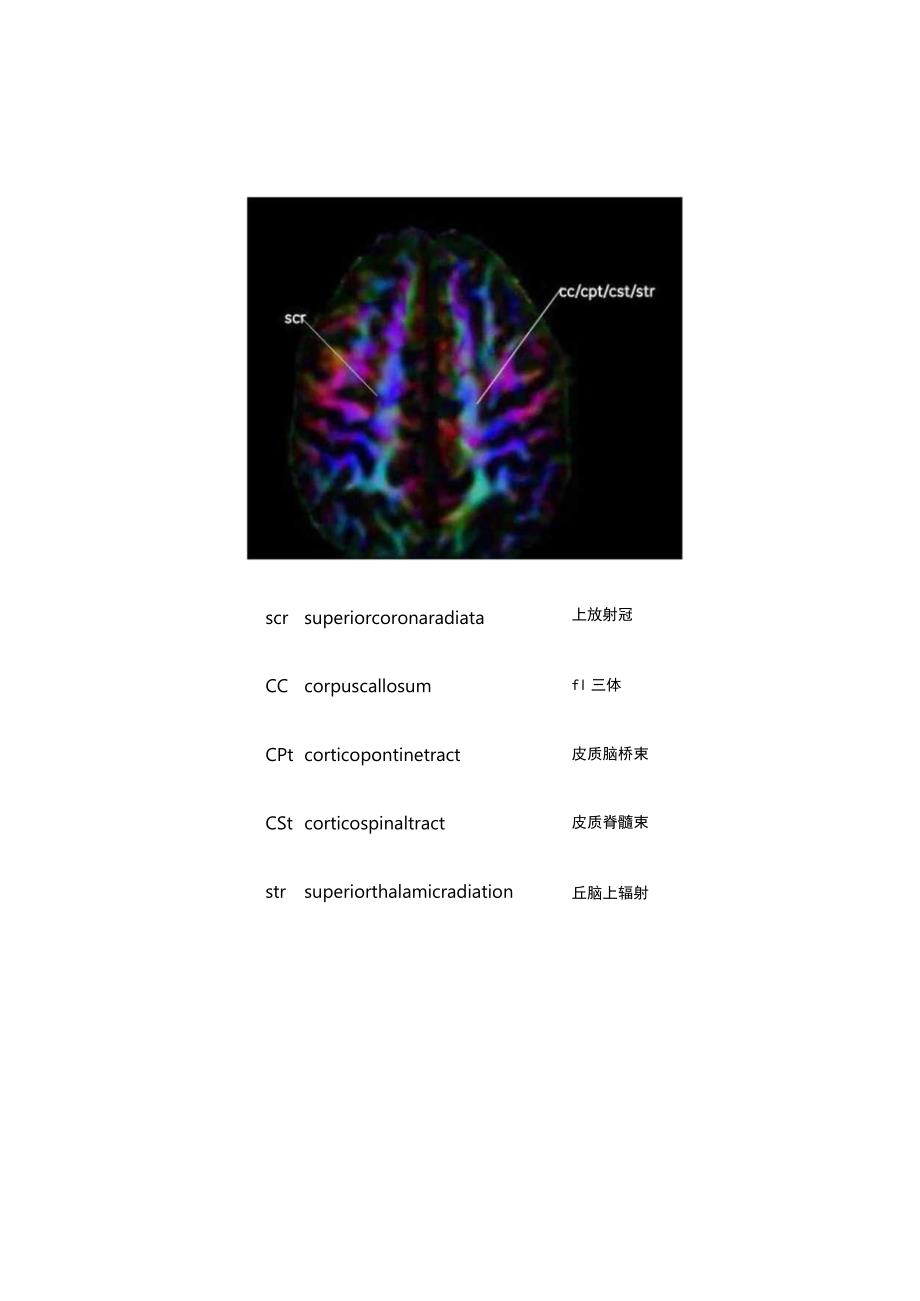

2、翻译)编辑此解剖图谱,希望对大家有用。本文是第一部分,为轴位高清DTI解剖图谱。后续会推出冠状和矢状位图谱,最终打算将其汇总为T分Pdf文档,方便查找。敬请期待!声明:本系列图谱图片来源于网络(几年前在网络上获取的,在我印象中来自GE官方教育网站,具体网址记不清了),同时也参考了一些外文资料,再此一并感谢。本文出于学习交流目的,图片版权归原作者所有。本文未经过严格校对,图文难免有错漏,同时英文简写全名也难免有误。还请大家指正。Axi-Iscrsuperiorcoronaradiata上放射冠CCcorpuscallosumfl三体CPtcorticopontinetract皮质脑桥束CStco

3、rticospinaltract皮质脊髓束strsuperiorthalamicradiation丘脑上辐射acranteriorcoronaradiata前放射冠丘脑前辐射anteriorthalamicradiationcccorpus callosum腑氐体cpt corticopontine tract皮质月齿桥束cst corticospinal tract皮质脊髓束perposterior corona radiata后放射冠ptrposteriorthalamicradiation丘脑后辐射strsuperiorthalamicradiation丘月圆上辐身寸acranterio